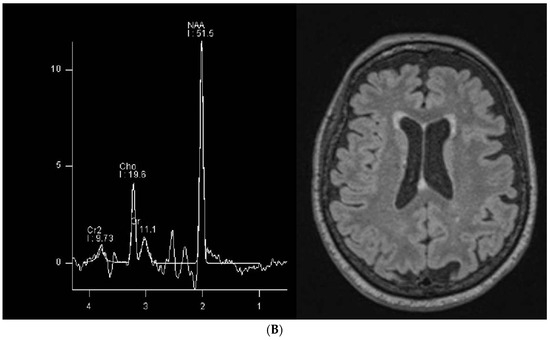

Selective Alteration of the Left Arcuate Fasciculus in Two Patients Affected by Creatine Transporter Deficiency

by Maurizio Balestrino, Enrico Adriano, Paolo Alessandro Alì and Matteo Pardini

Brain Sci. 2024, 14(4), 337; https://doi.org/10.3390/brainsci14040337 - 30 Mar 2024

(1) Background: In hereditary creatine transporter deficiency (CTD), there is an absence of creatine in the brain and neurological symptoms are present, including severe language impairment. However, the pathological changes caused by creatine deficiency that generate neuropsychological symptoms have been poorly studied. (2) [...] Read more.

(1) Background: In hereditary creatine transporter deficiency (CTD), there is an absence of creatine in the brain and neurological symptoms are present, including severe language impairment. However, the pathological changes caused by creatine deficiency that generate neuropsychological symptoms have been poorly studied. (2) Aims: To investigate if the language impairment in CTD is underpinned by possible pathological changes. (3) Methods: We used MRI tractography to investigate the trophism of the left arcuate fasciculus, a white matter bundle connecting Wernicke’s and Broca’s language areas that is specifically relevant for language establishment and maintenance, in two patients (28 and 18 y.o.). (4) Results: The T1 and T2 MRI imaging results were unremarkable, but the left arcuate fasciculus showed a marked decrease in mean fractional anisotropy (FA) compared to healthy controls. In contrast, the FA values in the corticospinal tract were similar to those of healthy controls. Although white matter atrophy has been reported in CTD, this is the first report to show a selective abnormality of the language-relevant arcuate fasciculus, suggesting a possible region-specific impact of creatine deficiency. Full article